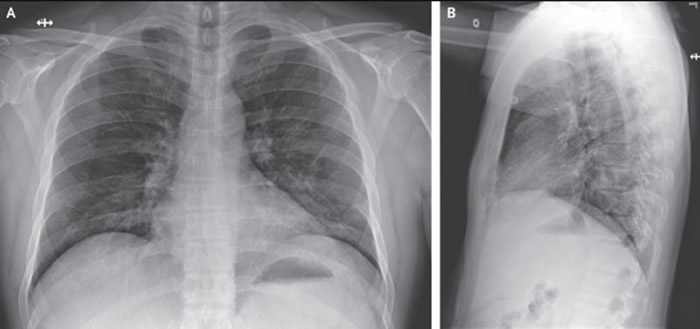

患者住院第6天的胸部X光

综合彭博等外媒报导,该名35岁男子先前曾赴武汉,并没有去过华南海鲜市场,但返美后出现咳嗽、发烧等症状,随后入住华盛顿州一间医疗中心的隔离病房接受观察治疗。然而,他的病情最初并未有明显改善,接续出现干咳、间歇发热伴随心搏过速等症状,到了入院第5天(患病第9天),X光检查显现出左肺下叶有着肺炎症状,呼吸道状态出现改变,并于第6天开始接受输氧。